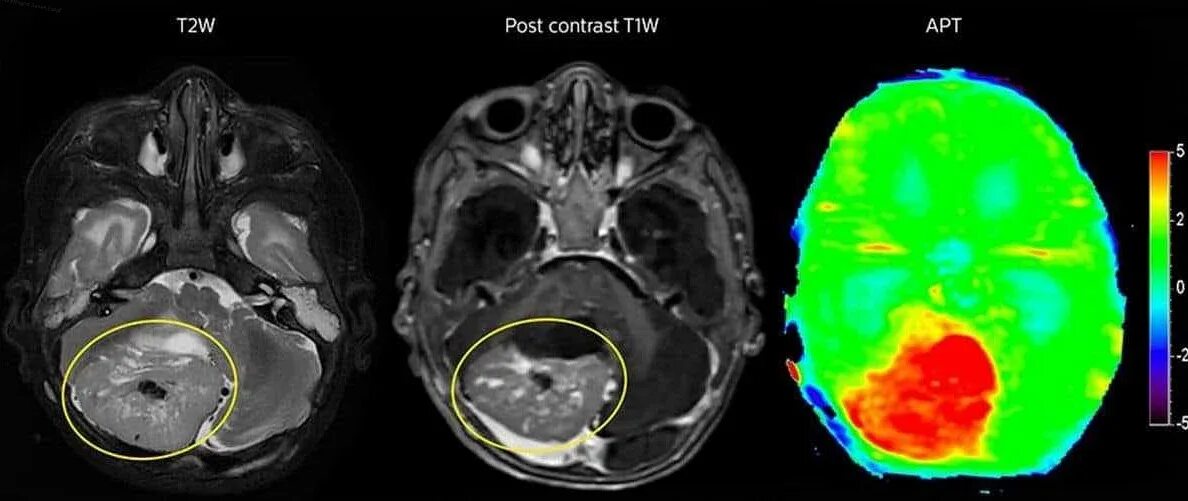

Как выглядит опухоль на снимках